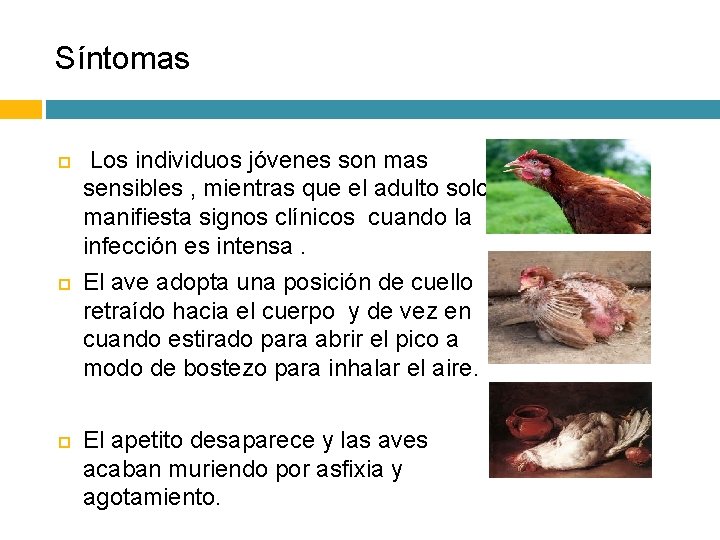

Síntomas Los individuos jóvenes son mas sensibles , mientras que el adulto solo manifiesta signos clínicos cuando la infección es intensa. El ave adopta una posición de cuello retraído hacia el cuerpo y de vez en cuando estirado para abrir el pico a modo de bostezo para inhalar el aire. El apetito desaparece y las aves acaban muriendo por asfixia y agotamiento.